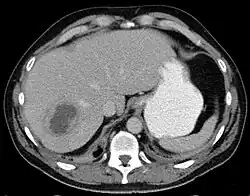

| Liver abscess on axial CT image: a hypodense lesion in the liver with peripherally enhancement. | |

A liver abscess is a mass filled with pus inside the liver.[1] Common causes are abdominal conditions such as appendicitis or diverticulitis due to haematogenous spread through the portal vein.[2] It can also develop as a complication of a liver injury.